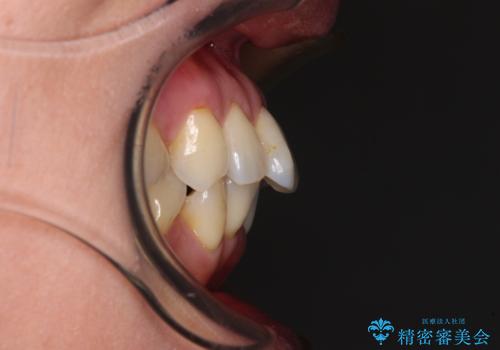

- 前方に飛び出した前歯を気にして来院された患者様です。

通常であれば上下左右の第一小臼歯4本を抜歯して口元の突出感を改善しますが、下顎前歯が1本欠損しており、上下の歯の数がアンバランスであるため、4本抜歯するかどうか悩むところでした。

上顎前歯はやや小さめで、下顎前歯はやや大きめであったため、上下左右4本を抜歯しても左右奥歯の咬み合わせは理想に近い状態を達成できると判断し、上下左右の第一小臼歯4本を抜歯し、ワイヤー装置にて矯正治療を行うこととしました。